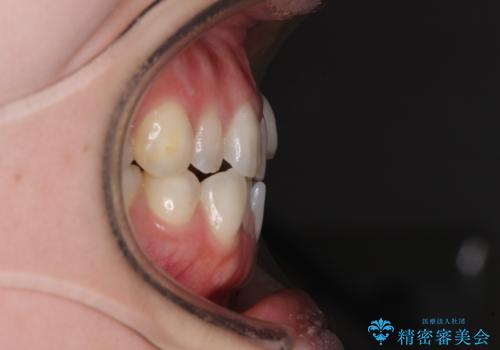

- 左上の八重歯と前歯のデコボコを気にして来院された患者様です。

下顎が左側にズレており、下顎前歯は1歯欠損していたため、左上小臼歯1本を抜歯し、ワイヤー装置にて矯正治療を行うこととしました。